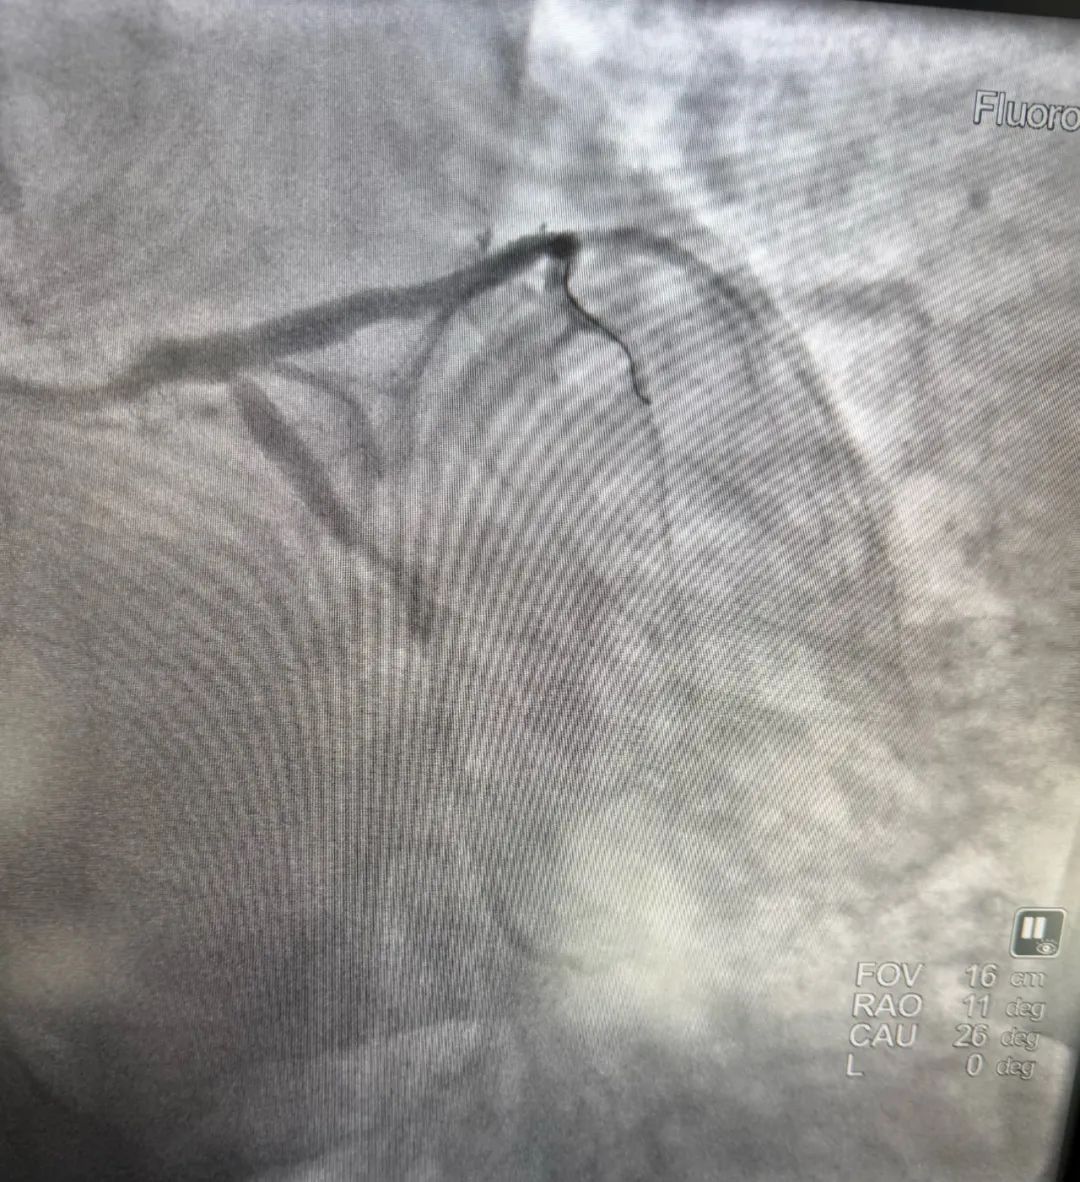

术后图

造影的结果正如我们预料的一样,前降支近端100%的闭塞。我们手术仅用时15分钟就快速地给病人开通了血管,植入了一枚支架。操作完成后,患者症状明显改善,心电图恢复正常,患者得救了。

看到病人转危为安,我们内心也充满了成就感。最后,我向所有在劳动节坚守岗位的劳动者致敬!祝所有劳动者节日快乐!